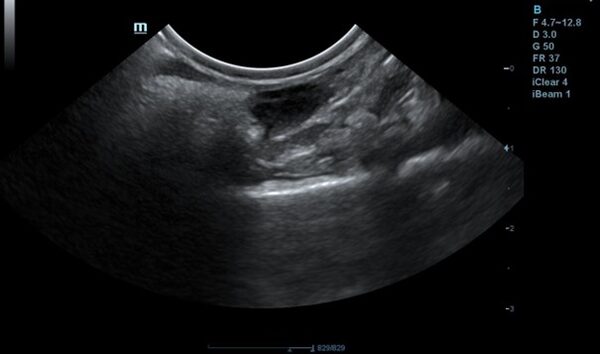

Tiger ist inzwischen ein 17-jähriger Europäisch-Kurzhaar-Kater. Letztes Jahr wurde er uns im Sommer wegen chronischer Magen-Darm-Beschwerden und Gewichtsverlusts vorgestellt. Trotz seines Alters scheuten seine Besitzer keine Kosten und Mühen. Im Ultraschall zeigten sich eine verdickte Darmwände, besonders die Muskelschicht war sehr dick (rote Markierung). Um der Ursache auf den Grund zu gehen, entnahmen wir Gewebeproben. Von dem Eingriff erholte sich Tiger sehr gut und die Wunden heilten ab.

Im Ultraschall ist deutlich zu sehen, dass die Darmwand nicht mehr verdickt und der Tumor unter Therapie derzeit unter Kontrolle ist.